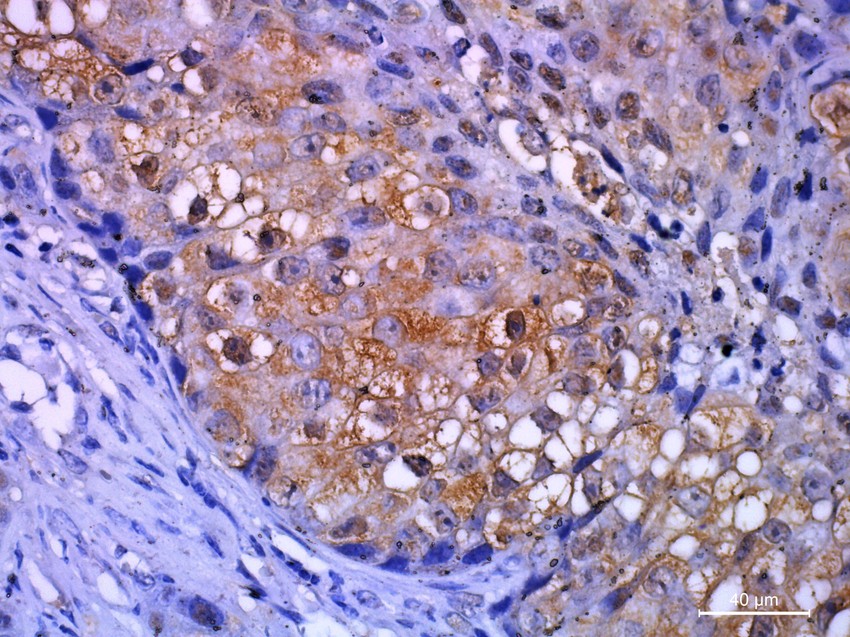

A patológusok egy immunhisztokémia nevű vizsgálatot végezhetnek a Helicobacter pylori baktériumok kimutatására a gyomor belső felszínén. Amikor ezt a vizsgálatot elvégzik, a baktériumok barna vagy vörös színűnek tűnnek, és lehetnek kerekek vagy vessző alakúak.

Az immunhisztokémiai festést a szövettanban használják kutatásra vagy diagnózisra.